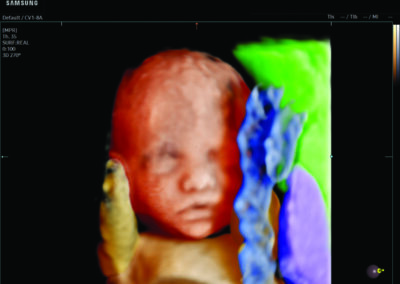

Comprehensive, advanced and expert MFM care for high-risk pregnancies